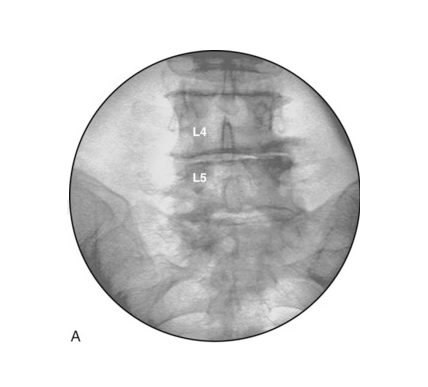

Fluoroscopy is a type of medical imaging that produces images similar to an X-ray These images can be dynamic to allow live monitoring of a procedure or still images to confirm that the target area has been successfully treated. Using fluoroscopy has significantly helped to deliver safer treatments and reduce the overall risks involved.

The patient would be positioned on a special X-ray-compatible table in an operating theatre. The area of the body to be treated would be examined and then imaged using the C-shaped fluoroscopy device.

We use X-ray guidance (fluoroscopy) to direct a very small needle into the targeted area. Once the correct position is confirmed, the medicine is injected, other nerve treatments can be applied and the needle is then removed.